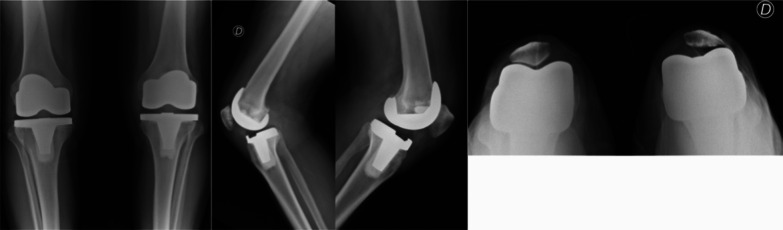

Background: Total knee arthroplasty (TKA) is the most effective treatment for end-stage adult knee osteoarthritis, but it has been reported that patient satisfaction may vary. A malfunction of the patellofemoral joint may produce anterior knee pain (AKP) for several reasons. While some surgeons systematically resurface the patella despite the risk of potential complications such as fracture, loosening, or wear of the patella, others prefer to preserve it to reduce AKP and revision rates. This study aimed to evaluate whether patellar resurfacing had better clinical and functional outcomes, complications, and revision rates in patients undergoing simultaneous bilateral total knee arthroplasty.

Methods: We conducted a prospective cohort study, including patients who underwent bilateral simultaneous TKA in which the patella was replaced in one knee and preserved in the other, with a minimum follow-up of 7 years. We assessed clinical and functional outcomes with the Knee Society Score (KSS) and Visual Analogue Scale (VAS); complications and revision rates were also registered.

Results: The final series consisted of 43 patients with 86 knee arthroplasties. After a mean of 7.6 years of follow-up, no significant differences were found regarding KSS (clinical: 82.8 ± 7.4 versus 83.2 ± 3.4, p = 0.92; functional 89.1 ± 8.2: versus 90.4 ± 6.8; p = 0.99), VAS (2.0 ± 0.9 versus 1.8 ± 1.0; p = 0.84), complications (10.5% versus 8.1%; p = 0.57), or revision rates (2.3% versus 2.3%; p = 0.99) when comparing patellar resurfacing versus retention.

Conclusion: In the context of total knee arthroplasty, patellar replacement did not demonstrate statistically significant differences concerning patellar retention in clinical nor functional outcomes, AKP, complications, or revision rates after a minimum of 7 years of follow-up.